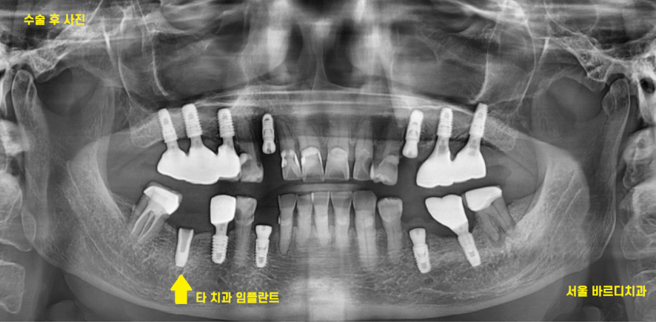

x-ray를 찍어보았습니다.

22.11.24

임플란트는 잘 남아있고

머리부분인 보철이 없어졌네요.

221219

뿌리만 남은 부분 뽑고 임플란트 한 사진입니다.